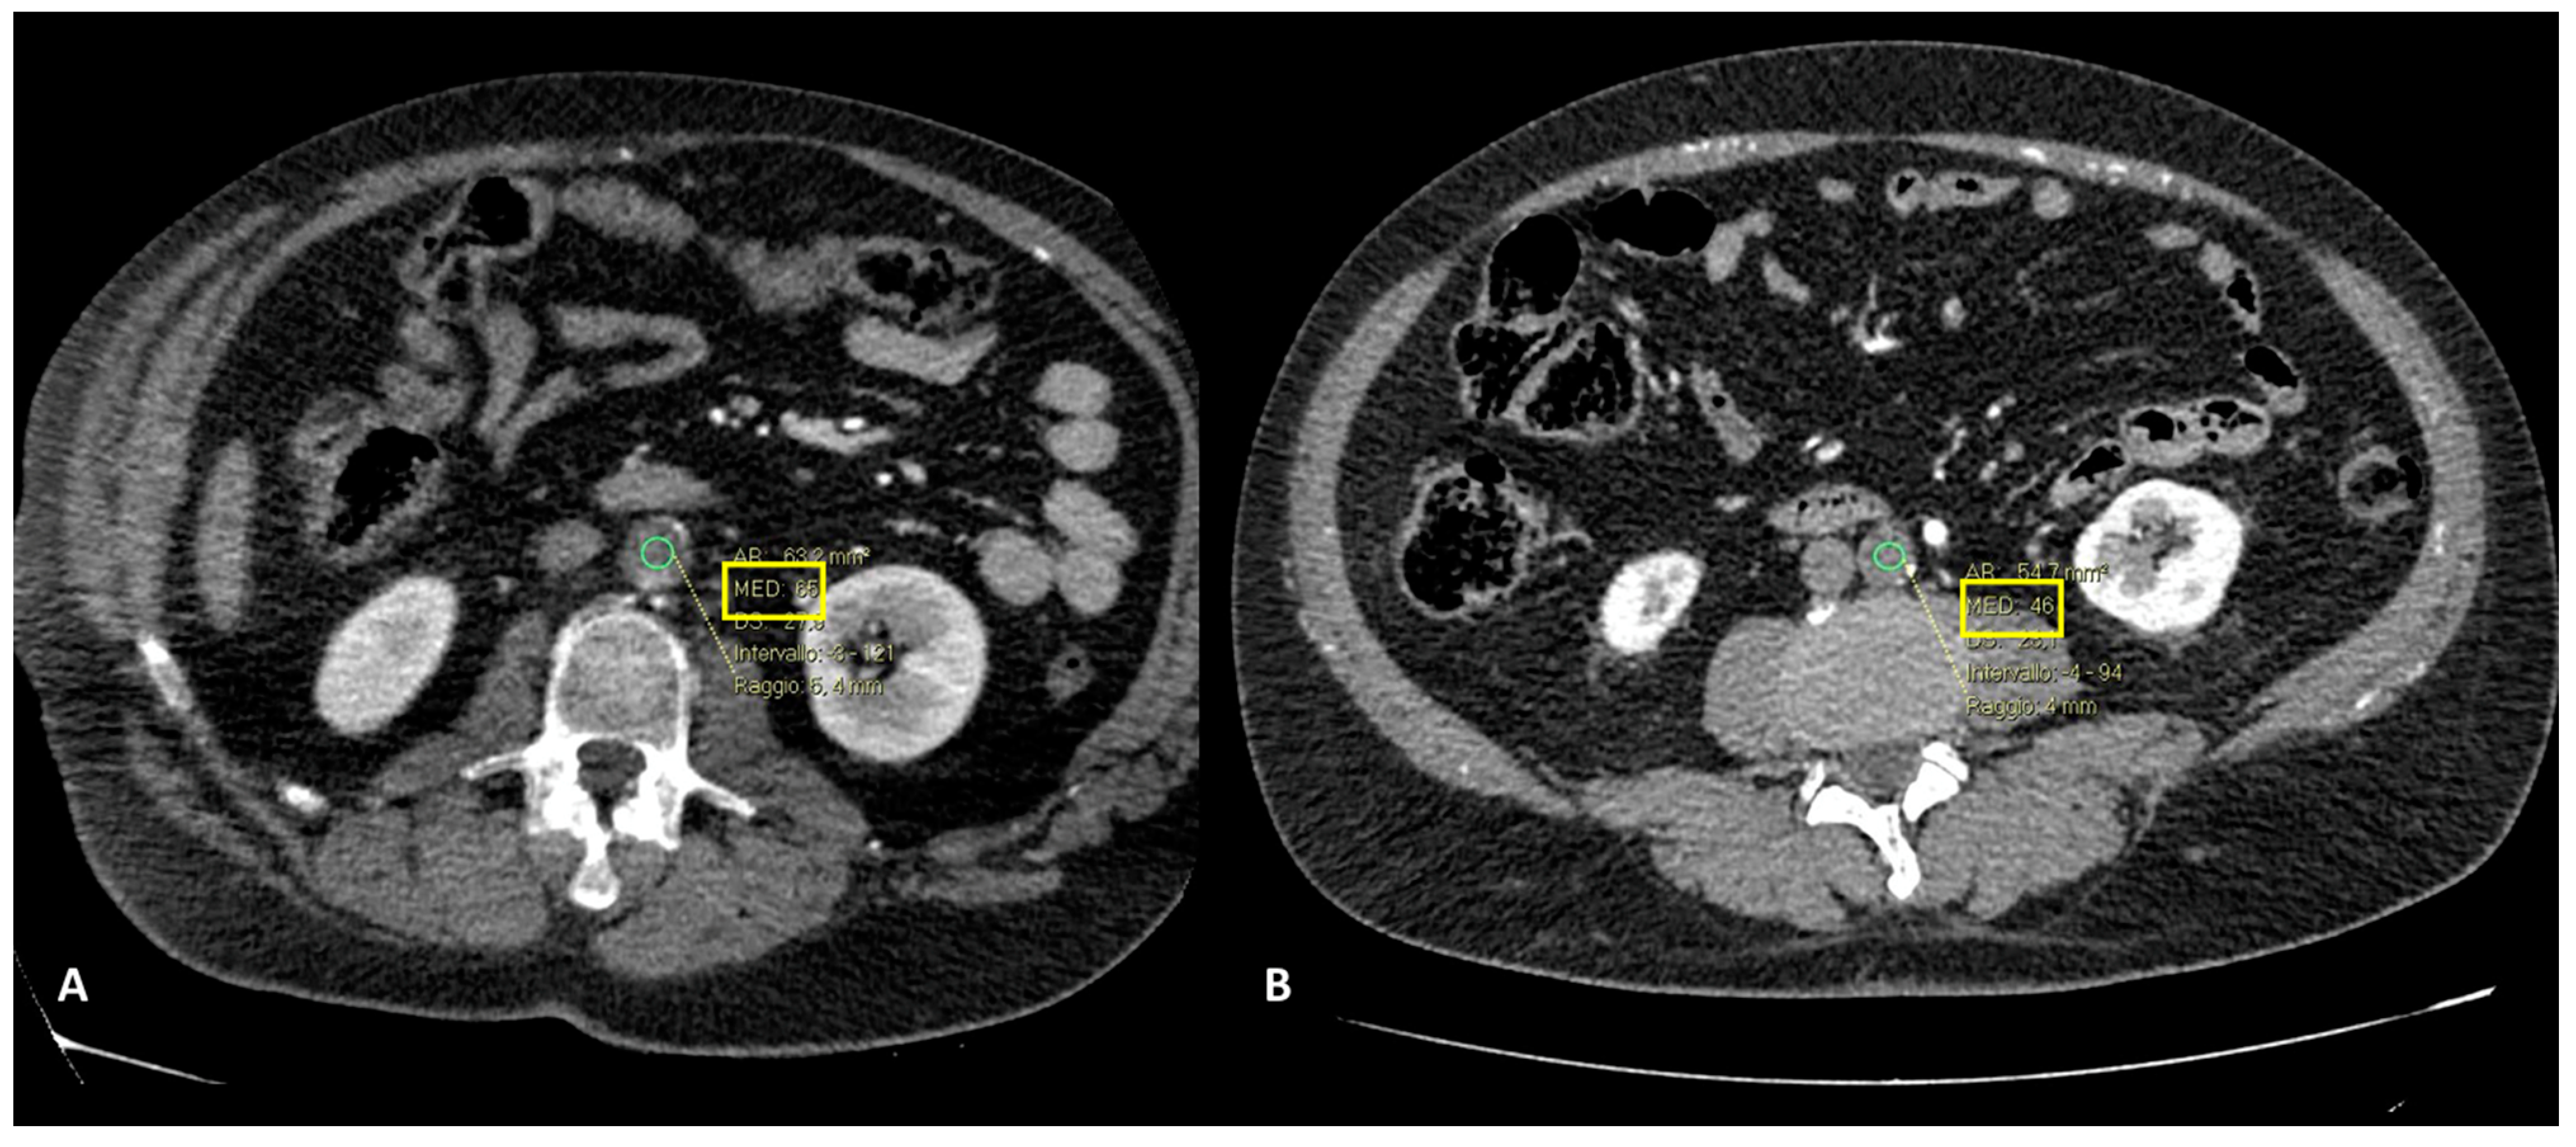

- Focal ischemia of the left renal parenchyma in four patients (36.4%) (Figure 3);